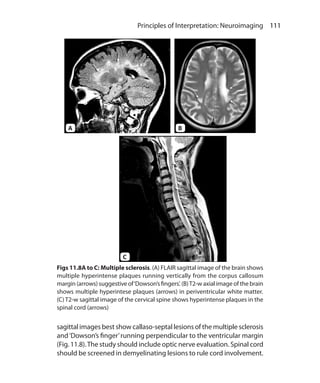

6  MRI MadeEasy (For Beginners) Slice Selection Gradient Sliceselectiongradienthasgraduallyincreasingmagneticfieldstrength from one end to another (Fig. 1.5). It determines the slice position. Slice thickness is determined by the bandwidth of RF pulse. Bandwidth is the range of frequencies. Wider the bandwidth thicker is the slice. Phase Encoding and Frequency Encoding Gradients These gradients are used to localize the point in a slice from where signal is coming. They are applied perpendicular to each other and perpendicular to the slice selection gradient (Fig. 1.6). Typically, for transverse or axial sections following are axes and gradients applied even though X and Y axes can be varied. Fig. 1.5: Slice selection gradient Fig. 1.6: Frequency and phase encoding gradients Ch-1.indd 6 25-09-2012 09:53:46

• 21.

7  Basic Principles 1. Z-axis—Slice selection gradient 2. Y-axis—Frequency encoding gradient 3. X-axis—Phase encoding gradient. In a usual sequence, slice selection gradient is turned on at the time of RF pulse. Phase encoding gradient is turned on for a short time after slice selection gradient. Frequency encoding or readout gradient is on in the end at the time of signal reception. Information from all three axes is sent to computers to get the particular point in that slice from which the signal is coming. Why Proton only? Other substances can also be utilized for MR imaging.The requirements are that their nuclei should have spin and should have odd number of protons within them. Hence theoretically 13C, 19F, 23Na, 31P can be used for MR imaging. Hydrogen atom has only one proton. Hence H+ ion is equivalent to a proton. Hydrogen ions are present in abundance in body water. H+ gives best and most intense signal among all nuclei. Ch-1.indd 7 25-09-2012 09:53:46

• 22.

T1, T2 Relaxations andImage Weighting CHAPTER 2 Relaxation means recovery of protons back towards equilibrium after been disturbed by RF excitation. Relaxation times of protons such as T1 and T2, and number of protons in tissues (proton density) are the main determinant of the contrast in an MR image. Asdiscussedinchapter1,RFpulsecausestiltingofmagnetizationin the transverse plane, where it rotates at Larmor frequency.This chapter discusses processes happening after this and their implications on the image contrast. What happens when RF pulse is switched off? When RF pulse is switched off, LM starts increasing along Z-axis and TM starts reducing in the transverse plane. The process of recovery of LM is called Longitudinal Relaxation while reduction in the magnitude of TM is called as Transverse Relaxation. The components of magnetization in longitudinal and transverse planes (i.e. LM andTM) can be represented by a single vector.This vector represents sum of these components and is called as netmagnetization vector (NMV). NMV lies some where between LM and TM. If there is no magnetization in transverse plane LM will be same as NMV. Similarly if there is no LM, TM will be equal to NMV. Longitudinal Relaxation When RF pulse is switched off, spinning protons start losing their energy.The low energy protons tend to align along the Z-axis. As more Ch-2.indd 8 13-09-2012 15:52:33